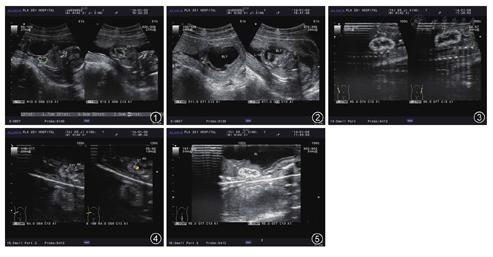

孕妇,28岁,孕1产0,孕18+4周,孕期未服药及接触有害物质,无遗传疾病家族史。产前超声检查示胎儿双顶径3.7 cm,头围13.7 cm,头颅环完整,无缺损变形,无脑积水;脊柱排列整齐,骶尾部未见异常;四肢可见(双手呈握拳状),股骨长度1.9 cm,肱骨长度2.0 cm;四腔心形态未见异常,胎心率168次/min。胎儿腹部明显膨隆,前腹壁菲薄,腹围15.2 cm(相当于孕20+1周);肝脏位置正常,胃泡及胆囊均可见;双肾可见(图1),右肾大小1.7 cm×0.9 cm,左肾大小2.0 cm×1.1 cm,双肾实质回声增强,左肾盂分离0.5 cm,右肾盂分离0.4 cm,双侧输尿管扩张,最宽处均为0.4 cm,胎儿下腹部及盆腔内可见一大小5.2 cm×4.6 cm×3.0 cm囊性包块(图2),边界清晰,形态不规整,内透声好,其两侧可见脐动脉通过。双侧输尿管均可见从两侧与下腹部盆腔内囊性包块相通,检查过程中双侧输尿管未见明显蠕动。胎盘位于前壁,羊水少。超声诊断:(1)中期妊娠,单活胎。(2)胎儿双肾实质回声增强,双肾轻度积水,双侧输尿管扩张,下腹部及盆腔内囊性包块,考虑为泌尿系统畸形:巨膀胱、下尿路梗阻。(3)考虑胎儿前腹壁发育不良。

注:RK为右肾;LK为左肾;BL为膀胱;R-UR为右侧输尿管;L-UR为左侧输尿管;ST为肾结石

超声检查后引产一男性胎儿,前腹壁菲薄,腹部塌陷,皮肤皱褶明显,外形无其他畸形。超声检查示胎儿双肾实质回声增强(图3),左肾中部可见一大小0.3 cm×0.2 cm结石强回声团(图4),后伴声影,双侧输尿管扩张,左侧为著,下腹部及盆腔内囊性包块(图5)无明显缩小,壁厚,较厚处厚度为0.3 cm,符合膀胱壁超声表现,腔内透声差可见密集点状回声。双侧输尿管均与下腹部及盆腔内囊性包块相通。胎儿标本解剖病理检查诊断为膀胱增大,与两侧输尿管相通;胎儿前腹壁发育不良,肌纤维缺如,仅见一层薄膜组织。综合本例胎儿前腹壁菲薄且皱褶明显、巨大膀胱、双侧输尿管扩张及双肾轻度积水考虑为梅干腹综合征(prune belly symdrome,PBS)。